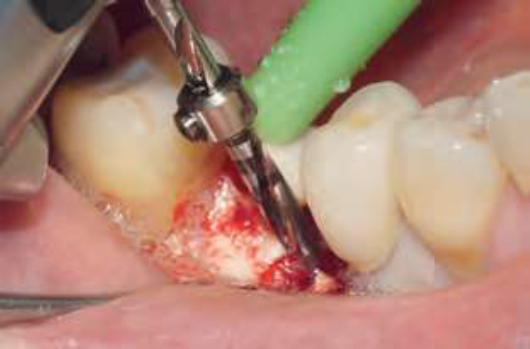

Inicialmente, após a antissepsia intraoral (digluconato de clorexidina a 0,12%) e extraoral (digluconato de clorexidina a 2%), uma anestesia terminal infiltrativa (mepivacaína 2% com epinefrina 1:100.000) foi administrada. Em seguida, o tecido gengival foi desinserido utilizando um descolador de Molt. Assim, um periótomo foi usado para remoção atraumática do dente 46, sem prejuízos à tábua óssea vestibular e lingual ou aos tecidos moles adjacentes. O alvéolo resultante foi curetado para remoção de toda a lesão de tecido granular e irrigado com solução fisiológica estéril (Figuras 3 e 4).